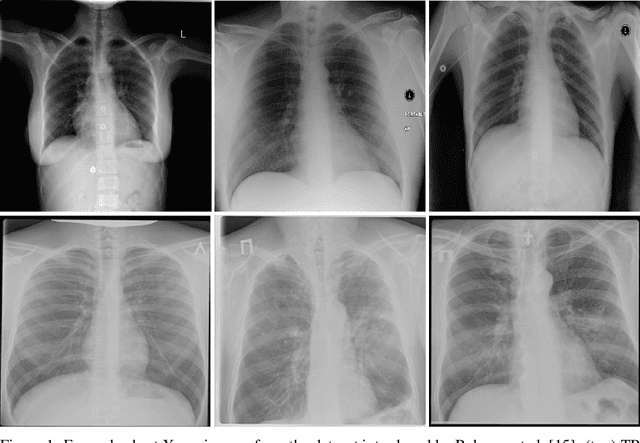

Abstract:Tuberculosis (TB) remains a global health problem, and is the leading cause of death from an infectious disease. A crucial step in the treatment of tuberculosis is screening high risk populations and the early detection of the disease, with chest x-ray (CXR) imaging being the most widely-used imaging modality. As such, there has been significant recent interest in artificial intelligence-based TB screening solutions for use in resource-limited scenarios where there is a lack of trained healthcare workers with expertise in CXR interpretation. Motivated by this pressing need and the recent recommendation by the World Health Organization (WHO) for the use of computer-aided diagnosis of TB, we introduce TB-Net, a self-attention deep convolutional neural network tailored for TB case screening. More specifically, we leveraged machine-driven design exploration to build a highly customized deep neural network architecture with attention condensers. We conducted an explainability-driven performance validation process to validate TB-Net's decision-making behaviour. Experiments on CXR data from a multi-national patient cohort showed that the proposed TB-Net is able to achieve accuracy/sensitivity/specificity of 99.86%/100.0%/99.71%. Radiologist validation was conducted on select cases by two board-certified radiologists with over 10 and 19 years of experience, respectively, and showed consistency between radiologist interpretation and critical factors leveraged by TB-Net for TB case detection for the case where radiologists identified anomalies. While not a production-ready solution, we hope that the open-source release of TB-Net as part of the COVID-Net initiative will support researchers, clinicians, and citizen data scientists in advancing this field in the fight against this global public health crisis.